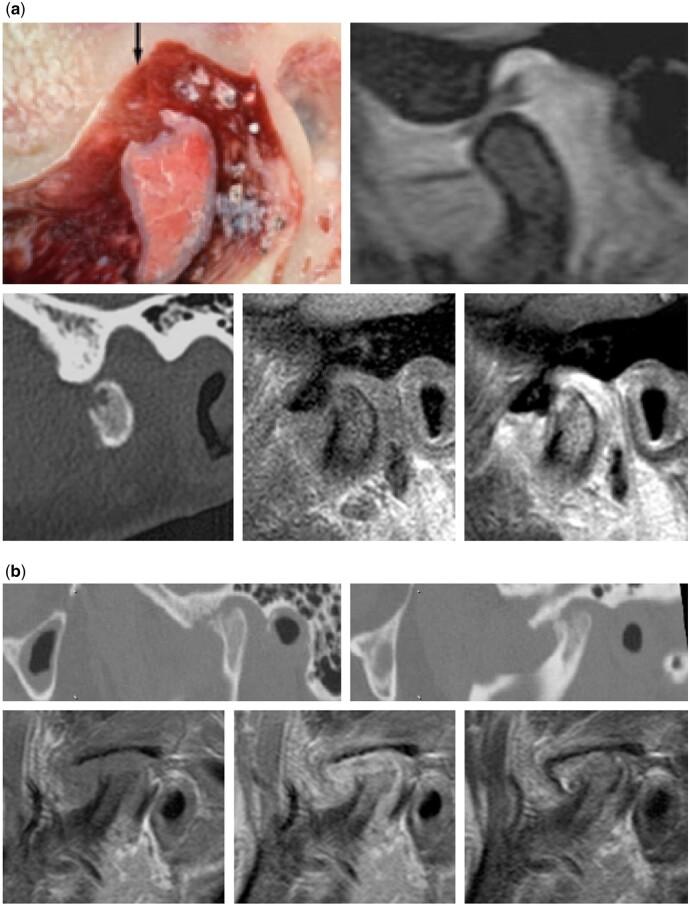

In this pictorial review, an introductory paragraph emphasizes the significance of some anatomical aspects for optimal imaging of the temporomandibular joint (TMJ). The most frequent pathologies: internal derangement (ID) and osteoarthritis (OA) are comprehensively discussed and illustrated. Less common conditions: ID and OA-like changes in children and adolescents, idiopathic condylar resorption, inflammatory arthritis, and juvenile idiopathic arthritis are briefly discussed. A short paragraph on differential diagnostics in young patients is included followed by a brief comment on expansile lesions that occasionally may occur in the TMJ.